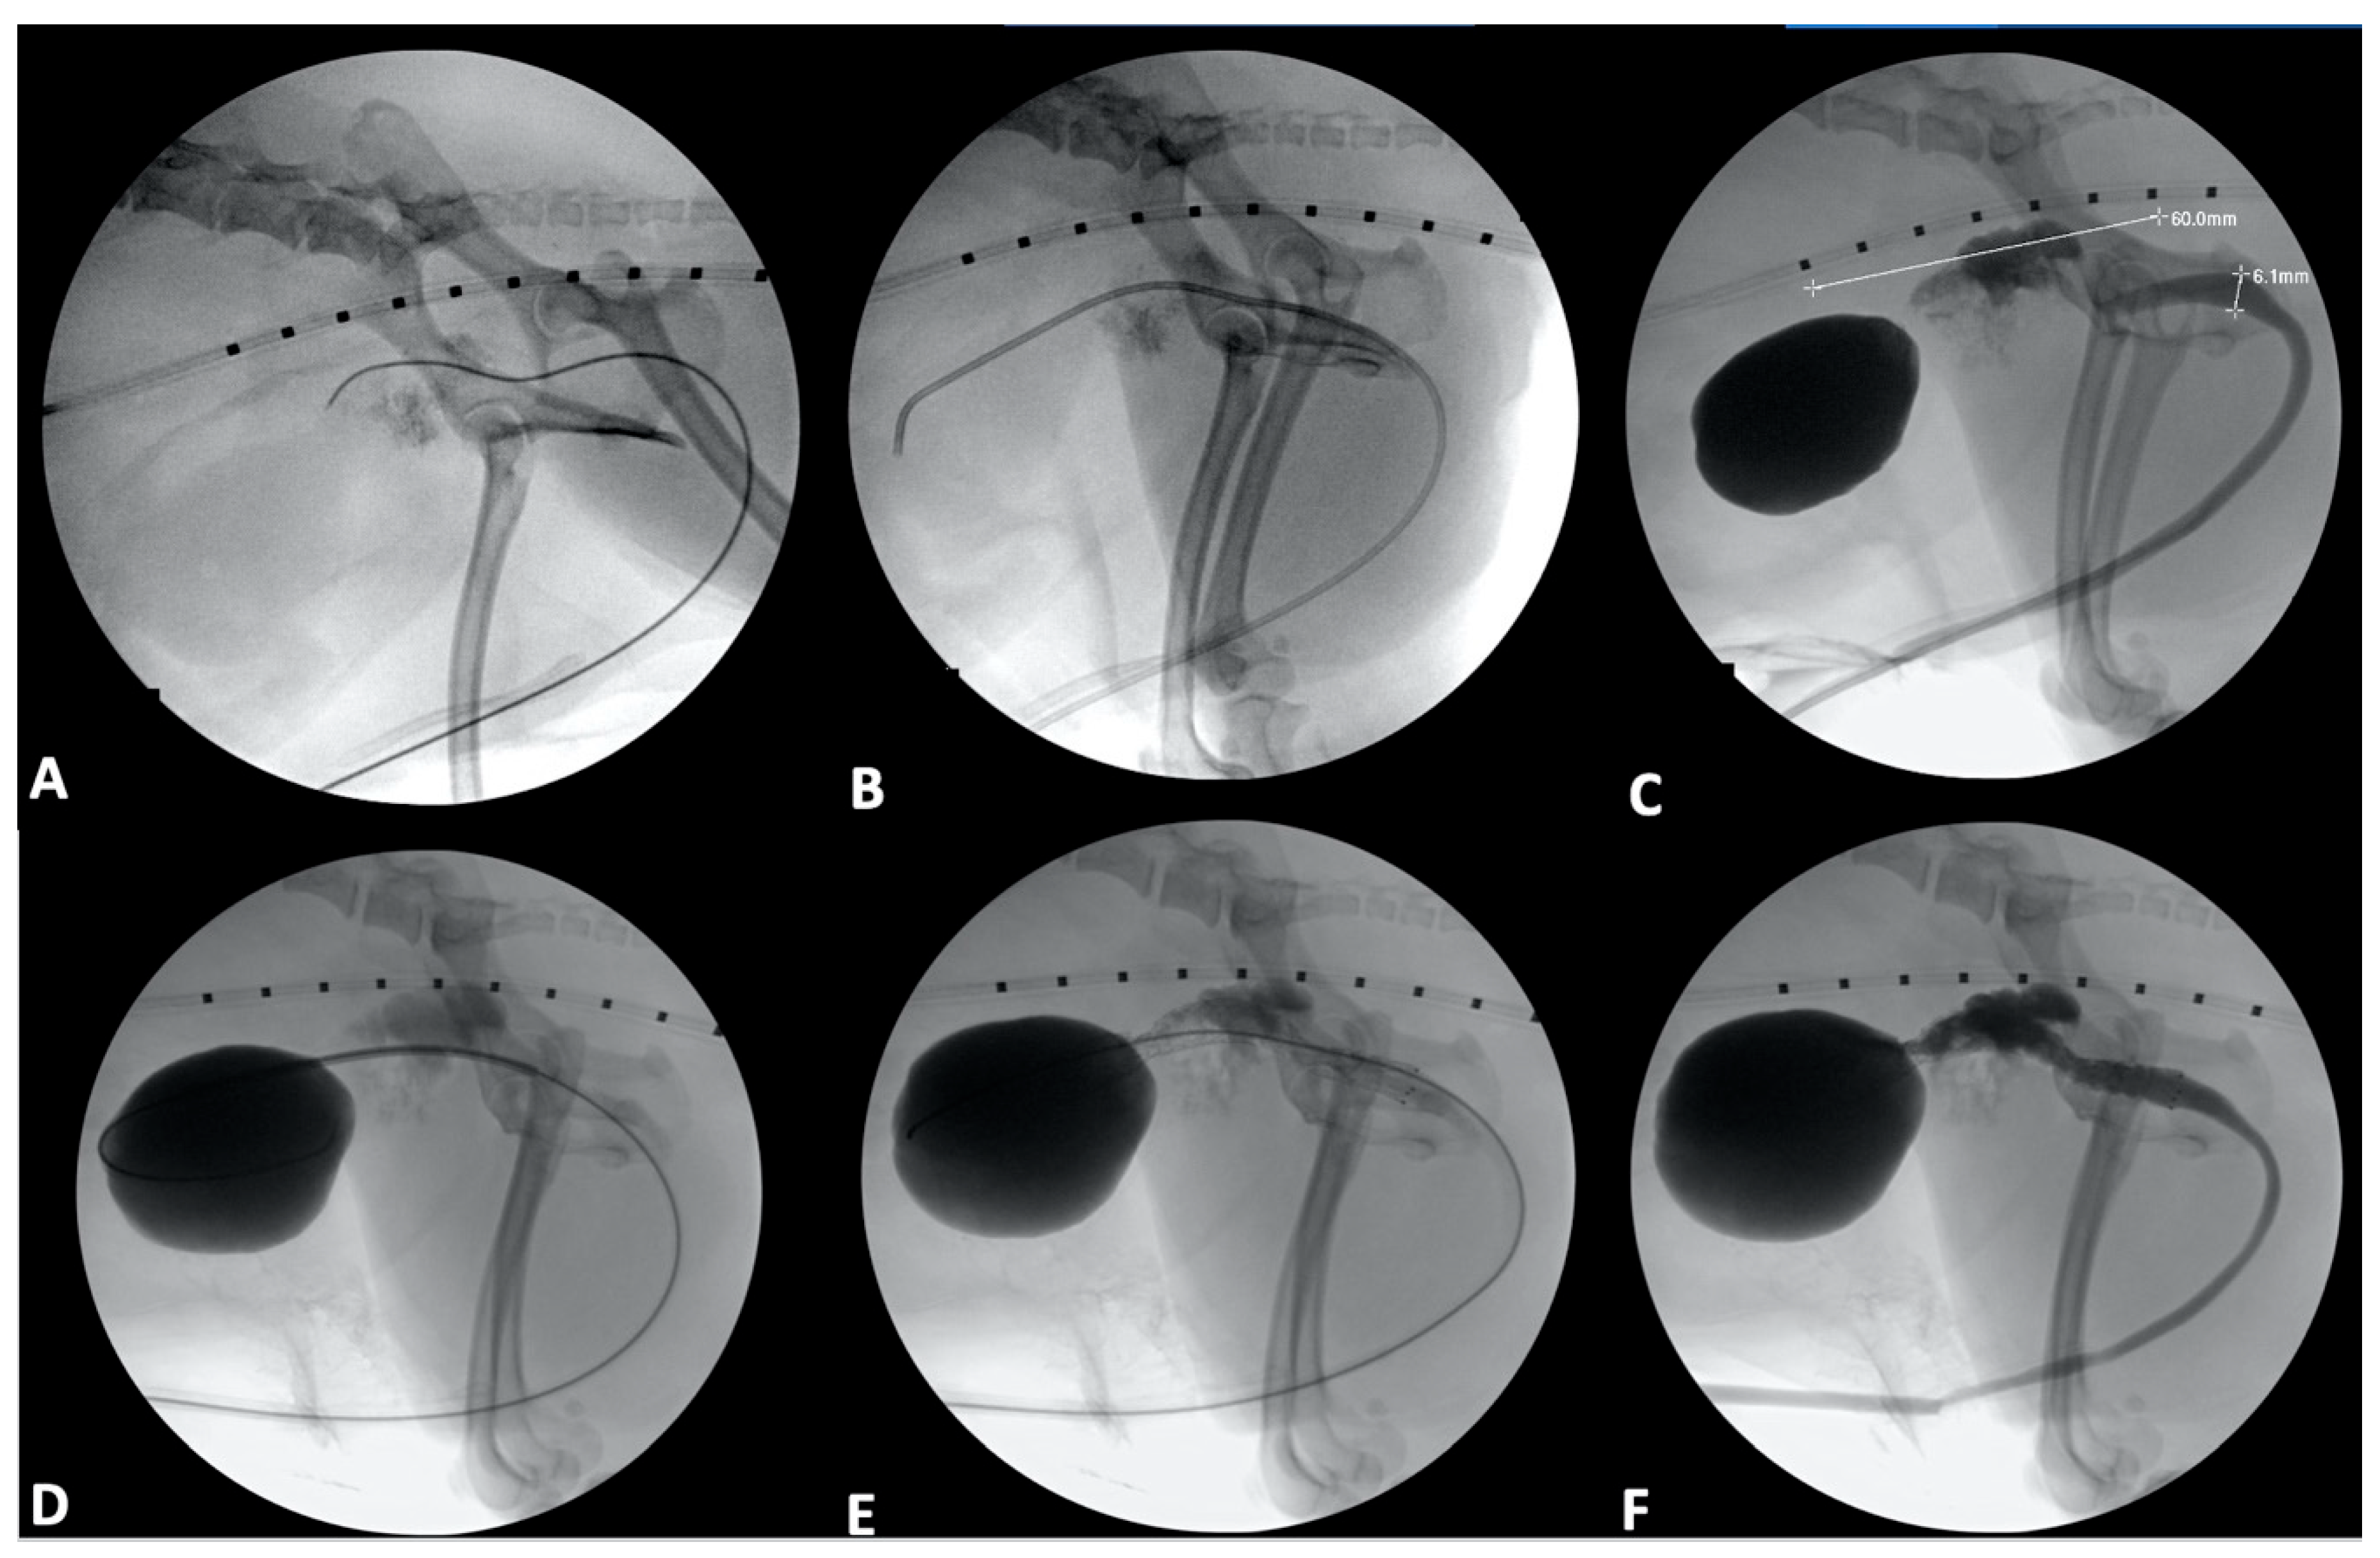

4.1. Ureter